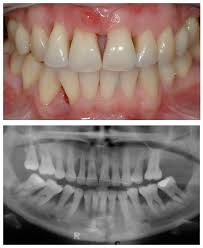

Dentist reveals new ways to control gum disease, even if past efforts have failed Natural ingredients · personal care · deep cleaning · no 1 Designed to deep clean gums. What is the treatment for severe gum disease? Is it possible to cure advanced gum disease? Advance white, essentials, complete care, sensitive teeth & gums Gum disease causes serious health risks. Removes harmful bacteria · dentist recommended Thanks to its mild, sweet flavor, coconut oil is preferred as a natural mouthwash over other oils such as sunflower or sesame oil. Apr 04, 2019 · one effective method for improving your gum disease and reversing periodontitis is oil pulling. Peroxicare™ removes plaque, whitens teeth, and helps reduce gum bleeding and redness. Dentist reveals new ways to control gum disease, even if past efforts have failed Many individuals have implemented coconut oil into their daily regimen.